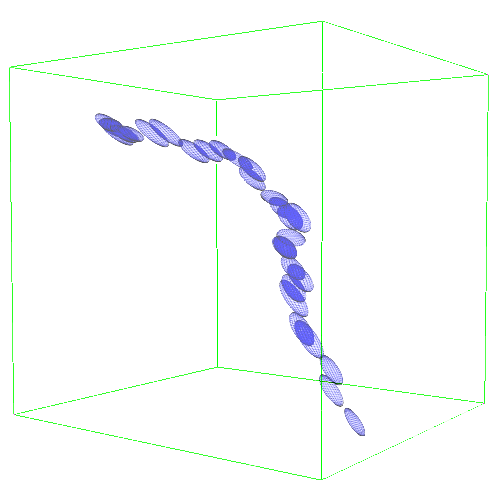

2.2 Vascular Tree of Geodesic Minimal Paths

Following the concepts first introduced in [4], we formulate an anisotropic front propagation algorithm that combined with an acyclic connectivity paradigm joins multiple sources propagating concurrently on a Riemannian speed potential . Since we want to extract geodesic minimal paths between points, we minimize an energy functional for any possible path between two generic points along its geodesic length, so that , and . The solution to the Eikonal partial differential equation is given here by the anisotropic Fast Marching (aFM) algorithm [4], where front waves propagate from on , with describing the infinitesimal distance along , relative to the anisotropic tensor . In our case, , and . Note that the anisotropic propagation is a generalised version of the isotropic propagation medium, . The acyclic connectivity paradigm is run until convergence together with the aFM to extract the vascular tree of multiple connected geodesics .

Geodesic paths are determined by back-tracing when different regions collide. The connecting geodesic is extracted minimizing at the collision grid-points. The aFM maps, i.e. ; the Voronoi index map , representing the label associated to each propagating seed; and the Tag , representing the state of each grid-point (Front, Visited, Far), are then updated within the collided regions, so that these merge as one and the front is consistent with the unified resulting region. This is continued until all regions merge.

Initialization. The seeds are aligned towards the vessels’ mid-line with a constrained gradient descent, resulting in an initial set of sources . All 26-connected components initialize the aFM maps, i.e., , , , and constitute also the initial geodesics .

Path Extraction. Collision is detected when Visited grid-points of different regions are adjacent. A connecting is determined by linking the back-traced minimal paths from the collision grid-points to their respective sources with a gradient descent on (fig. 2). The associated integral geodesic length is computed and the connectivity in is updated in the form of an adjacency list. Lastly, the grid-points of the extracted are further considered as path seeds in the updating scheme, since furcations can occur at any level of the connecting minimal paths.

Fast Updating Scheme. A nested aFM is run only in the union of the collided regions using a temporary independent layer of aFM maps, where , , and . Ideally, the nested aFM is run until complete domain exploration, however, to speed up the process, the propagation domain is divided into the solved and unsolved sub-regions, and the update is focused on the latter (fig. 2). The boundary geodesic values of equal the geodesic distances at the collision grid-points. Lastly, the aFM maps are updated as: , , and .

The respective tensor fields (TF) synthesized on both HCP and PC show consistent features. The TF’s characteristics are in line with the connectedness of CVM: enhanced and connected vessels are associated with high anisotropy, whereas background areas show a predominant isotropic component.

3.2 Connected Geodesic Paths as Vascular Tree

Representative examples of degraded synthetic images from SVT and the respective GT are shown in fig. 4 together with the connected graphs extracted by VTrails. Analogously, the same set of images are reported for the real images TOF and CTA in fig. 4. Qualitatively, the extracted set of connected geodesic paths shows remarkable matching with the provided GT in all cases. First, we verify the acyclic nature of the graph. We found no cycles, degenerate graphs and unconnected nodes, meaning that the extracted connected geodesic paths represent a connected geodesic tree. Precision and recall are then evaluated for the identified branches. Also, error distances are determined as the connected tree’s binary distance map evaluated at GT. Average errors () precision and recall are reported (meanSD) in table 1. Note that no pruning of any spurious branches is performed in the analysis.